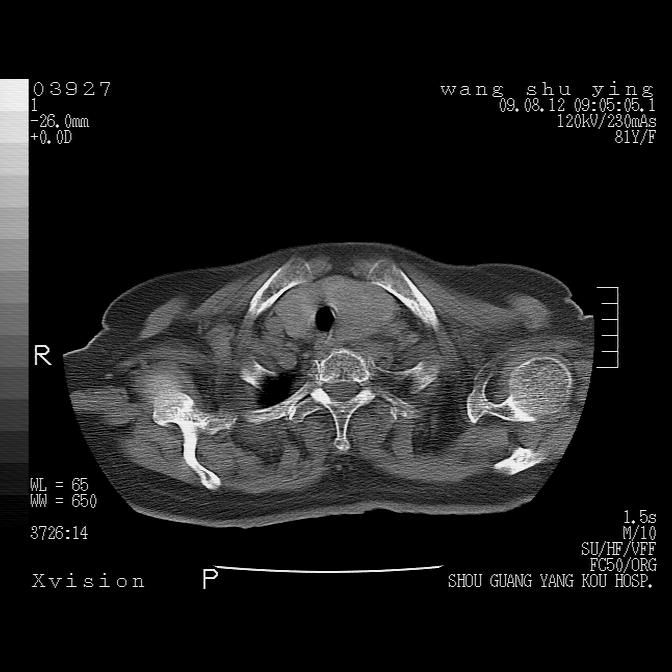

以下是引用帅河马在2009-8-12 12:59:00的发言:[br]两肺感染性病变伴双侧胸膜肥厚。[br]左侧甲状腺腺瘤不除外。[br]腹水+心包积液。[br][br][本贴已被 帅河马 于 2009-8-12 13:14:32 修改过]

以下是引用sdzyy在2009-8-12 18:17:00的发言:[br]两肺感染性病变伴双侧胸膜肥厚。[br]左侧甲状腺腺瘤不除外。[br]腹水+心包积液。[br]支持

以下是引用随光逐影在2009-8-12 19:42:00的发言:[br]1)两肺感染性病变伴双侧胸膜肥厚。2)不排除左侧甲状腺腺瘤。3)肝脏占位性病变;建议行进一步检查。